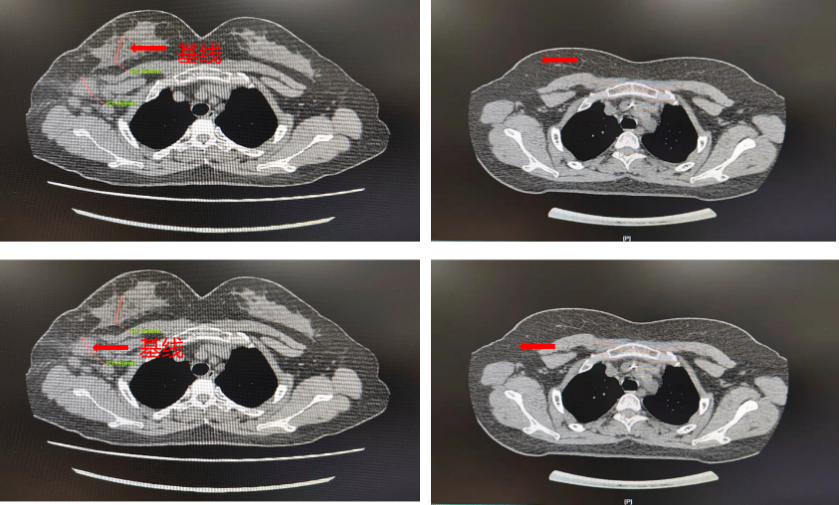

▌影像学评估(CT):

图4. 基线与6周期治疗后CT影像

图5. 基线与4周期治疗后MRI影像

乳腺组织中未见浸润性癌或原位癌残留,见纤维化及炎细胞浸润,治疗反应(重度,MP分级:5级);腋窝淋巴结未见癌转移(0/17),其中2枚淋巴结见纤维组织增生及泡沫样细胞反应。病理评估结果为pCR。

该患者为初诊HER2阳性IIB乳腺癌患者,经过国产曲妥珠单抗(汉曲优)联合帕妥珠单抗6周期新辅助治疗,治疗期间患者耐受性良好,影像学评估CR,行乳腺癌改良根治术后,术后病理MP评分为5级,提示已达pCR,说明汉曲优疗效等同于原研曲妥珠单抗,安全性相似,可以放心使用。